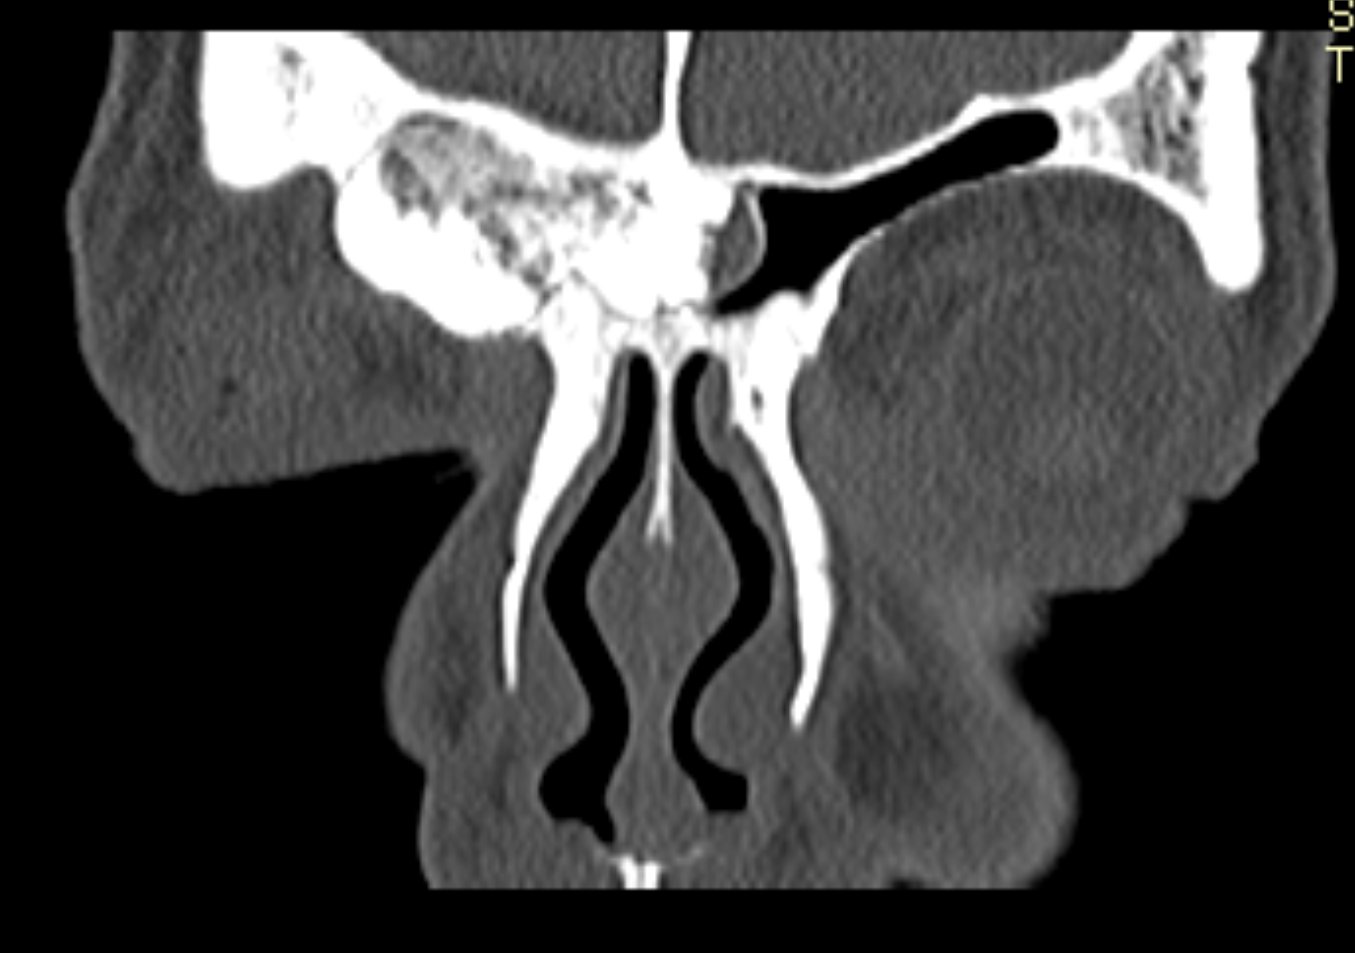

Examenul clinic ORL și examenele imagistice complementare (CT, RMN sinusuri paranazale) pun în evidență o formațiune tumorală osteogenică a sinusului frontal drept, protruzivă în unghiul supero-intern al orbitei, extinsă medial către sinusul frontal stâng.